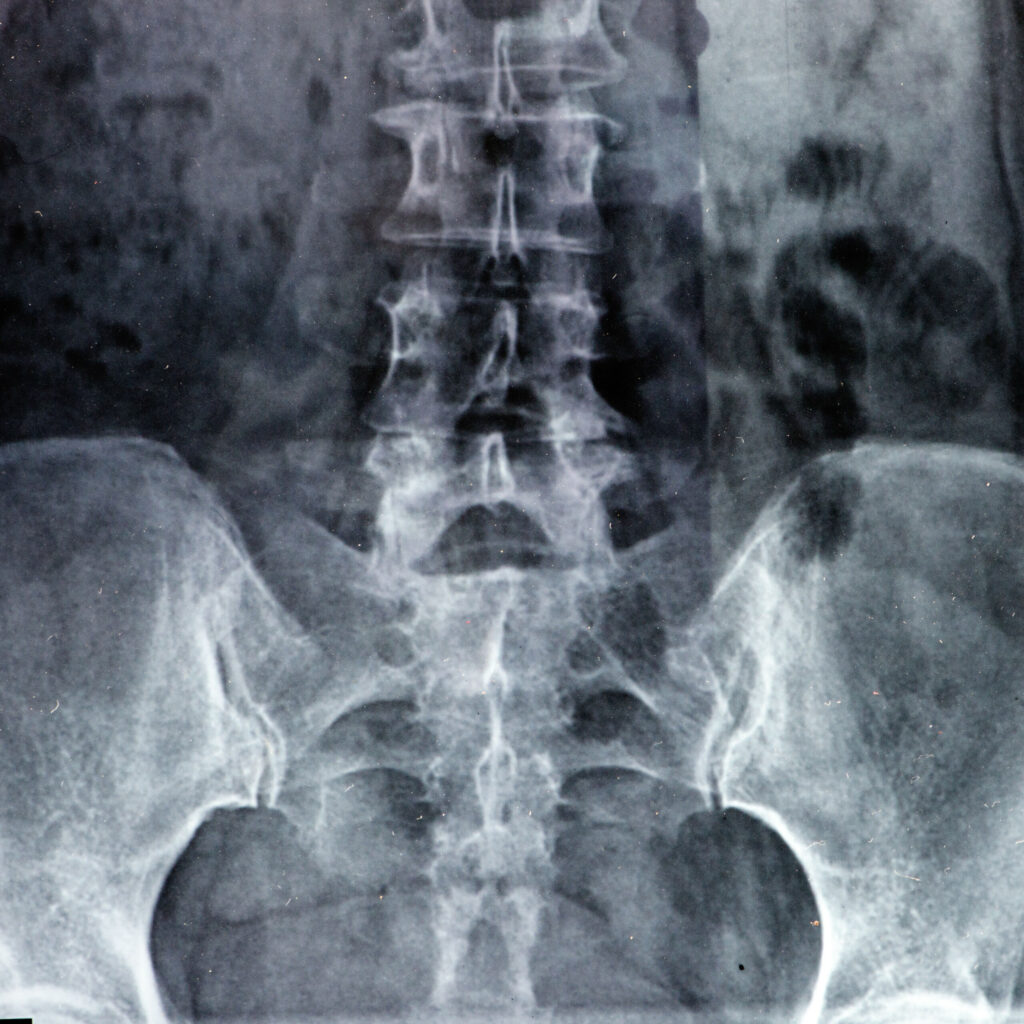

Cauda Equina Syndrome Claims